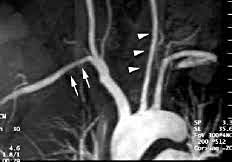

Основным методом инструментальной диагностики при болезни Такаясу служит артериография. С ее помощью подтверждают диагноз, а также оценивают состояние сосудов в динамике. Необходимо исследование всей аорты: изменения проявляются сужением длинных участков или окклюзией артерий, области аорты и устьев ее висцеральных ветвей. Используют также допплеровское ультразвуковое ангиосканирование и МРТ. Их преимущество — в способности диагностировать заболевание на ранней стадии. Гистологически болезнь Такаясу проявляется пан артериитом с локализацией инфильтрата преимущественно в адвентиции и наружных слоях меди, однако если результаты ангиографии и клинические симптомы типичны, то биопсия сосуда не требуется.